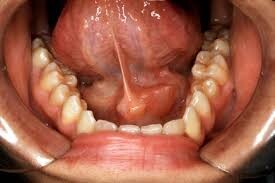

Salivary gland infections can result from blocked ducts. In these cases, swelling of the gland may be accompanied by redness and pus.

More rarely, salivary gland swelling occurs due to a tumor. Merck Manuals explains that swelling caused by a cancerous or noncancerous tumor on the salivary glands may be firmer than swelling caused by an infection. A cancerous tumor will likely be very hard and fixed to the gland tissue, while a noncancerous tumor may be movable.